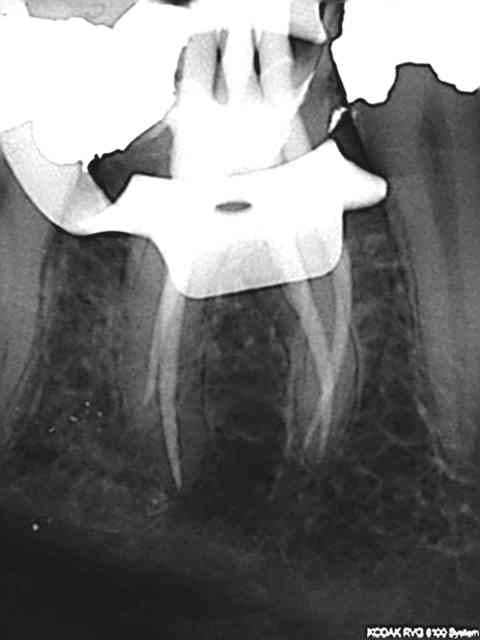

Juste pour prouver qu'on peut tout faire avec Mc Spadden, le derviche écossais:

Canal large, on est allé au F5 sans toucher les bords, cône calibré à 55 à l'apex, thermocompacteur à 3mm de la LT. Pas d'anesthésie.

21 ckpvf9 - Eugenol

Je l'utilise de mieux en mieux mais c'est vrai qu'il y a une petite douleur ressentie par les patients. Je descend super bas, mais je vérifie que j'ai un bon tug back à chaque fois (je descends à 2-4 mm de l'apex), avec un 40 ou un 30 la plupart du temps.